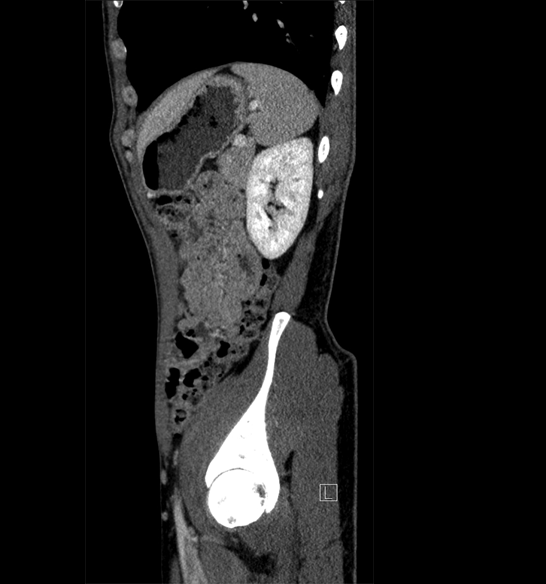

Body

Covers abdominal CT anatomy.